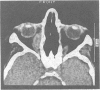

The standard description of Wegener's granulomatosis emphasises renal failure and thus a distorted impression may be given. Subacute and even chronic cases occur, and in these patients the presentation is varied and often insidious, leading to delay in diagnosis. Twenty two such patients (13 women and nine men) with a mean age of 44 years were seen in our connective tissue disease clinic. The mean duration of symptoms before diagnosis was 3.6 years and the mean duration of disease 5.9 years (19 years in one patient). All patients had malaise and ear, nose, and throat symptoms, and most had joint pains. Impaired renal function was seen in seven patients only. Tissue biopsy was diagnostic in half of the patients, and appreciably high titres of antineutrophil cytoplasmic antibodies were detected in only nine of 18 patients in whom these were measured. The most useful investigations were neutrophil counts, chest radiographs, and computed tomography of the sinuses and orbits. The most effective treatment was with intravenous pulses of cyclophosphamide. No deaths occurred. At the time of writing two patients were in remission and no longer being treated and 18 patients were in partial remission on continued treatment. Patients with subacute forms of Wegener's granulomatosis present with a variety of clinical features and the insidious presentation often leads to delay in diagnosis. A history of ear, nose, and throat symptoms was universal in our patients.